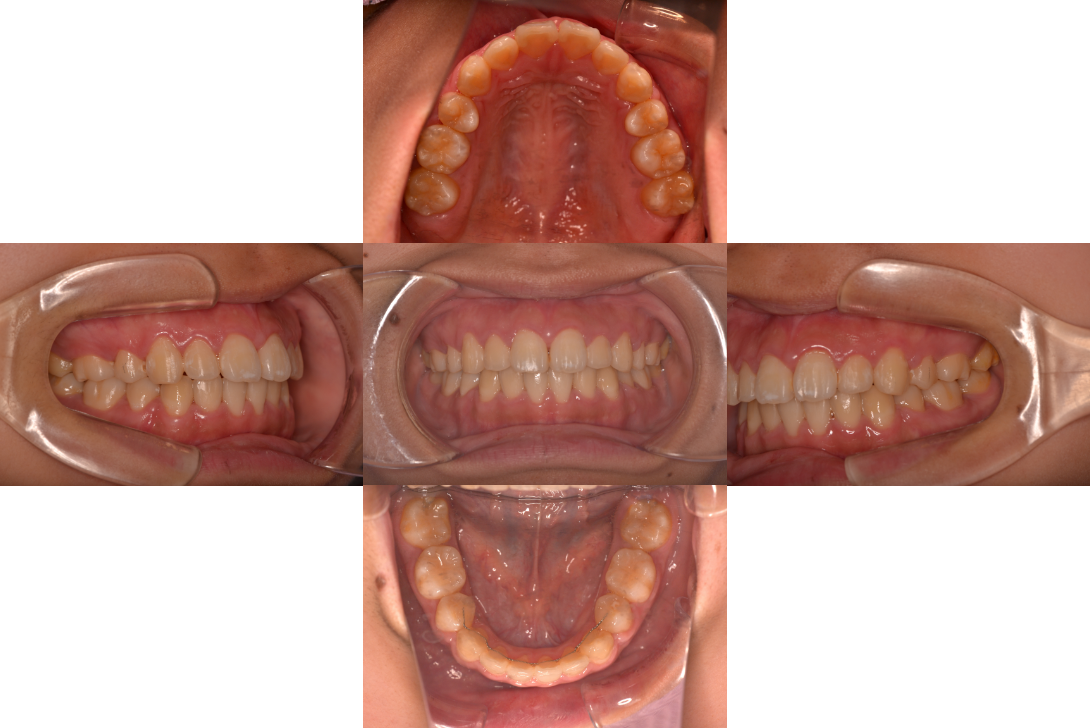

上顎前突(出っ歯)を抜歯とDBSで改善した症例

※DBSとはダイレクトボンディングシステムと呼ばれており、ブラケットにワイヤーを通して歯を動かしていく矯正治療です。

患者情報

16歳女性

主訴

口元下げたい

行った治療内容

上下顎両側4番抜歯、DBS

治療のリスク

歯根吸収、前歯部歯肉退縮

治療期間

動的治療期間2年9か月

※ クリックして拡大することができます。